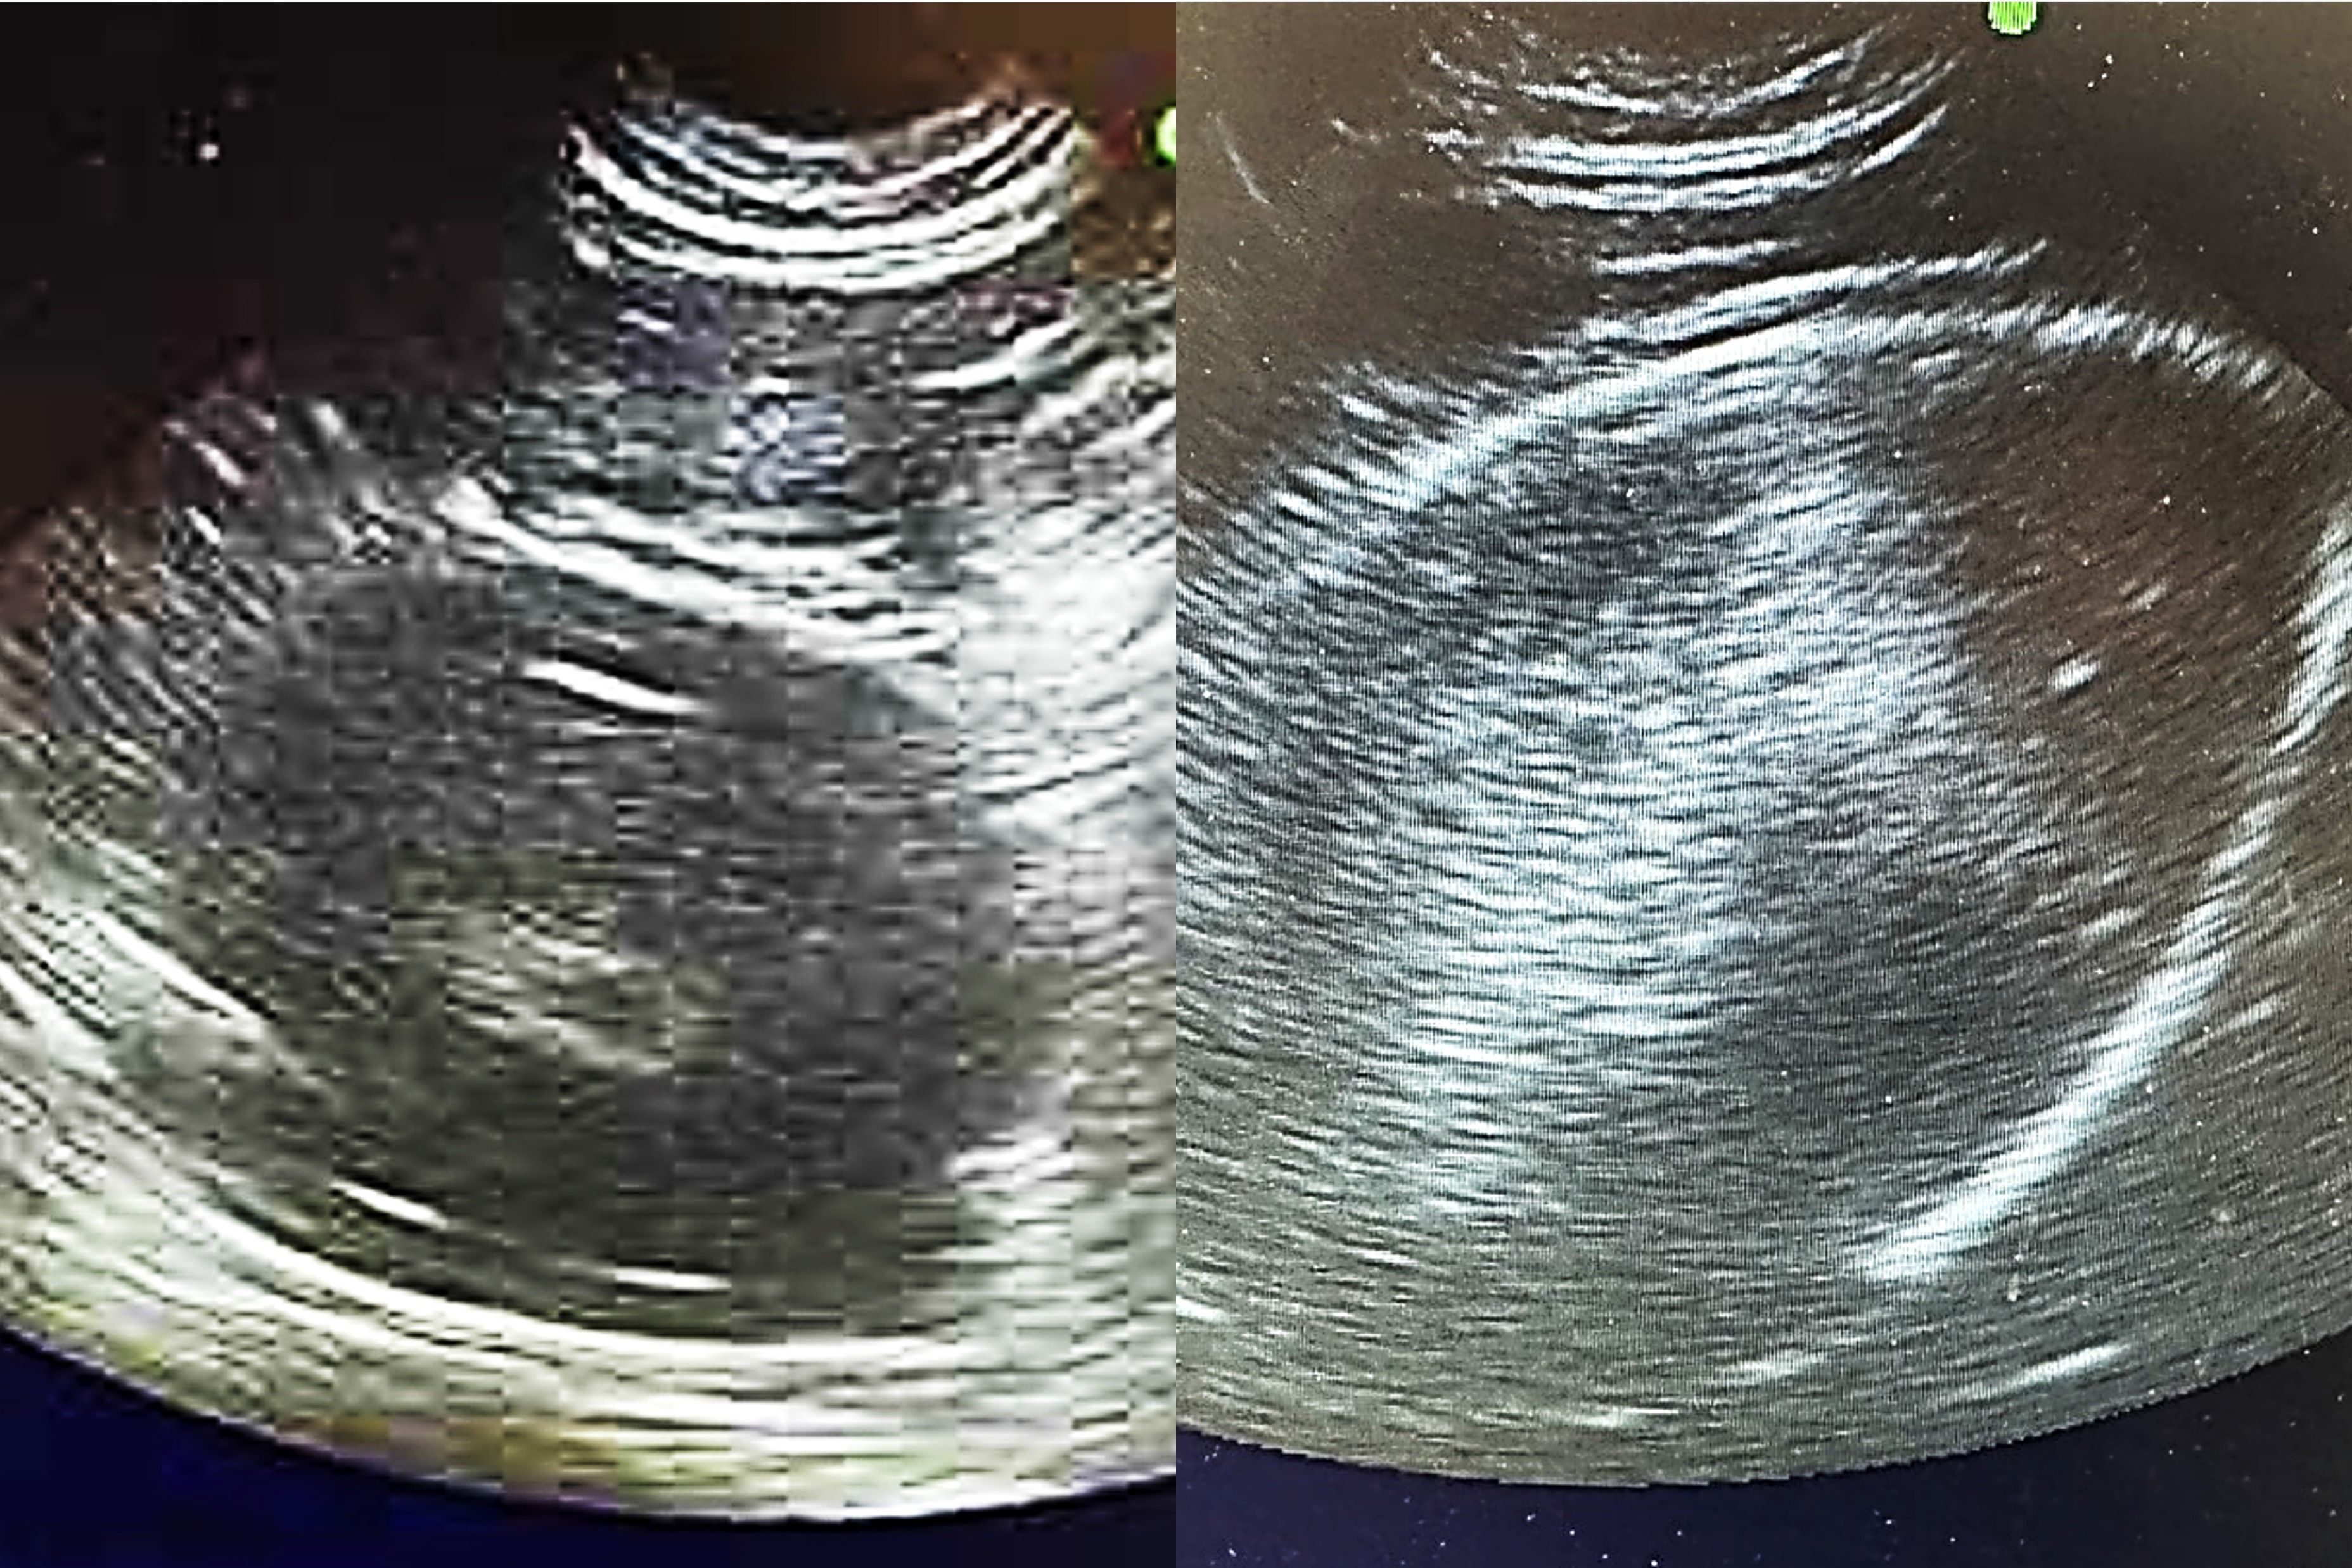

卵のエコー画像 左:産卵まであと4日ほどの卵 右:産卵まであと3日以内の卵

左の画像には卵黄だけが見えています。このような時は産卵まであと4日ほど。右の画像のように卵の殻がくっきり写っていると、3日以内くらいには産卵します。このエコー検査の時間は毎年すごくわくわくすると同時に、画面に小さな新しい命の影をみて「愛おしい…絶対に守り抜く!」と決意を新たにします。